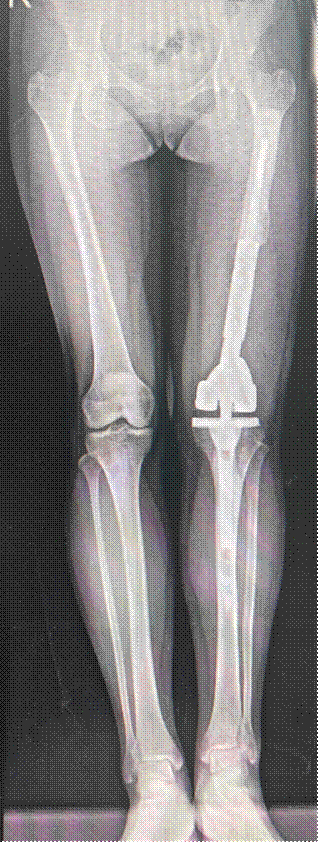

患者董女士(32岁)两年前因左股骨皮质旁骨肉瘤行保肢手术,术后四年影像学提示肿瘤复发。由于瘤体巨大,外院大多建议行截肢手术。

患者抱着一丝希望,慕名到同济大学附属同济医院骨科副主任袁锋专家门诊就诊。在完善术前检查后发现,患者股动脉及股静脉嵌顿于肿瘤缝隙之中。鉴于患者保肢欲望强烈,袁锋带领蔡涛等相关团队术中经过仔细操作,在完整切除肿瘤的前提下,成功分离出肿瘤缝隙中的股动脉及股静脉,为患者进行了铰链式膝关节假体置换,成功完成了患者的保肢手术。

术前影像学

术后影像学